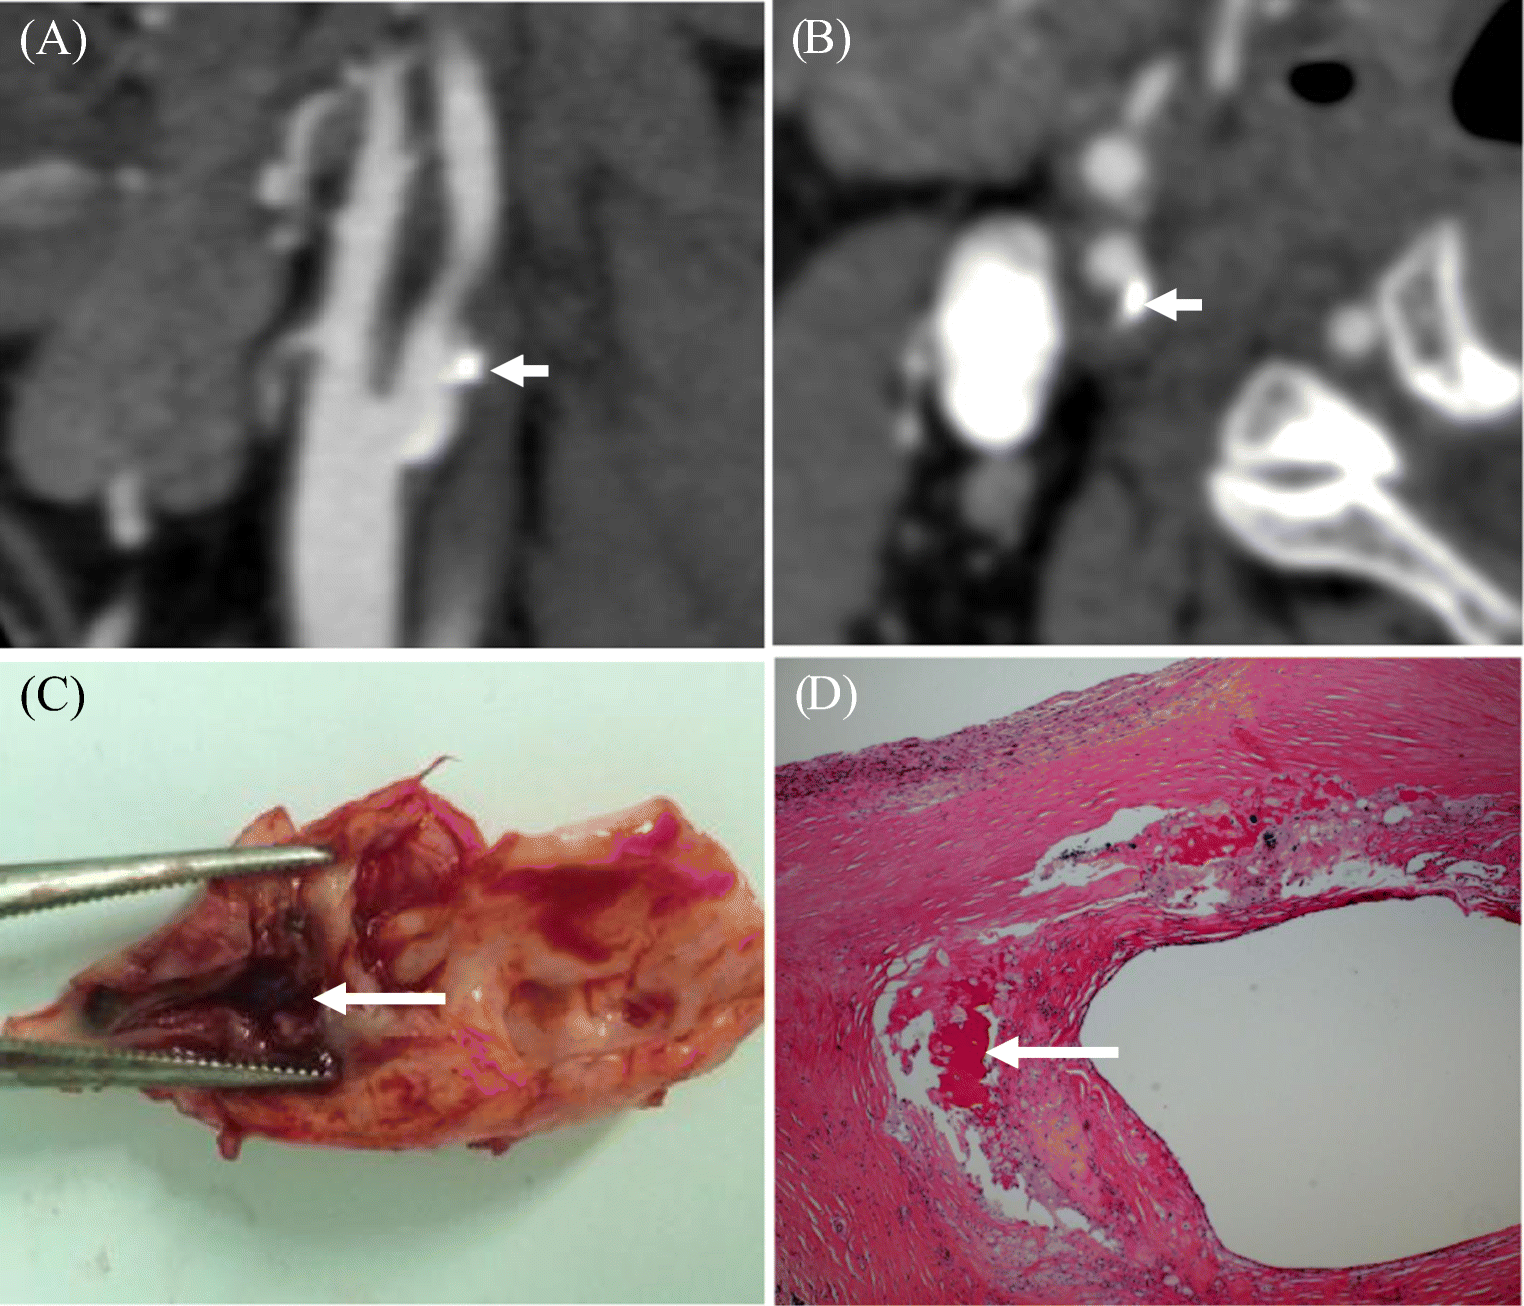

Differentiation of plaque ulceration, intraplaque hemorrhage, and... Download Scientific Diagram Plaque Ulceration carotid artery disease occurs when fatty deposits, called plaques, clog the blood vessels that deliver blood to the brain. a plaque ulceration is a defect in the fibrous cap of a plaque, defined as being an indentation, erosion, or fissuring of the luminal surface of the. here, we report the first case of healing of human carotid. Plaque Ulceration.

Plaque ulceration. (A) Shallow ulcer appearing as a focal depression or... Download Scientific Plaque Ulceration carotid artery disease occurs when fatty deposits, called plaques, clog the blood vessels that deliver blood to the brain. imaging findings in a symptomatic patient with ulcerated carotid plaque. a plaque ulceration is a defect in the fibrous cap of a plaque, defined as being an indentation, erosion, or fissuring of the luminal surface of the. . Plaque Ulceration.